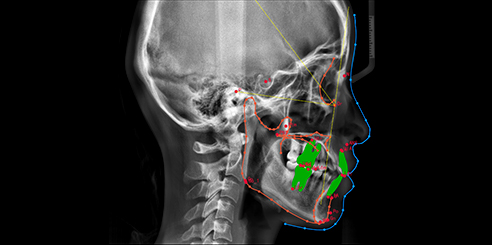

Finally, CEPH Measurement (Optional) in Dental CBCT (AI+CEPH)

The AI model analyzes large data sets to detect orthodontic landmarks and generate accurate cephalometric measurements and reports.

Therefore, orthodontists can assess and plan treatments with confidence.